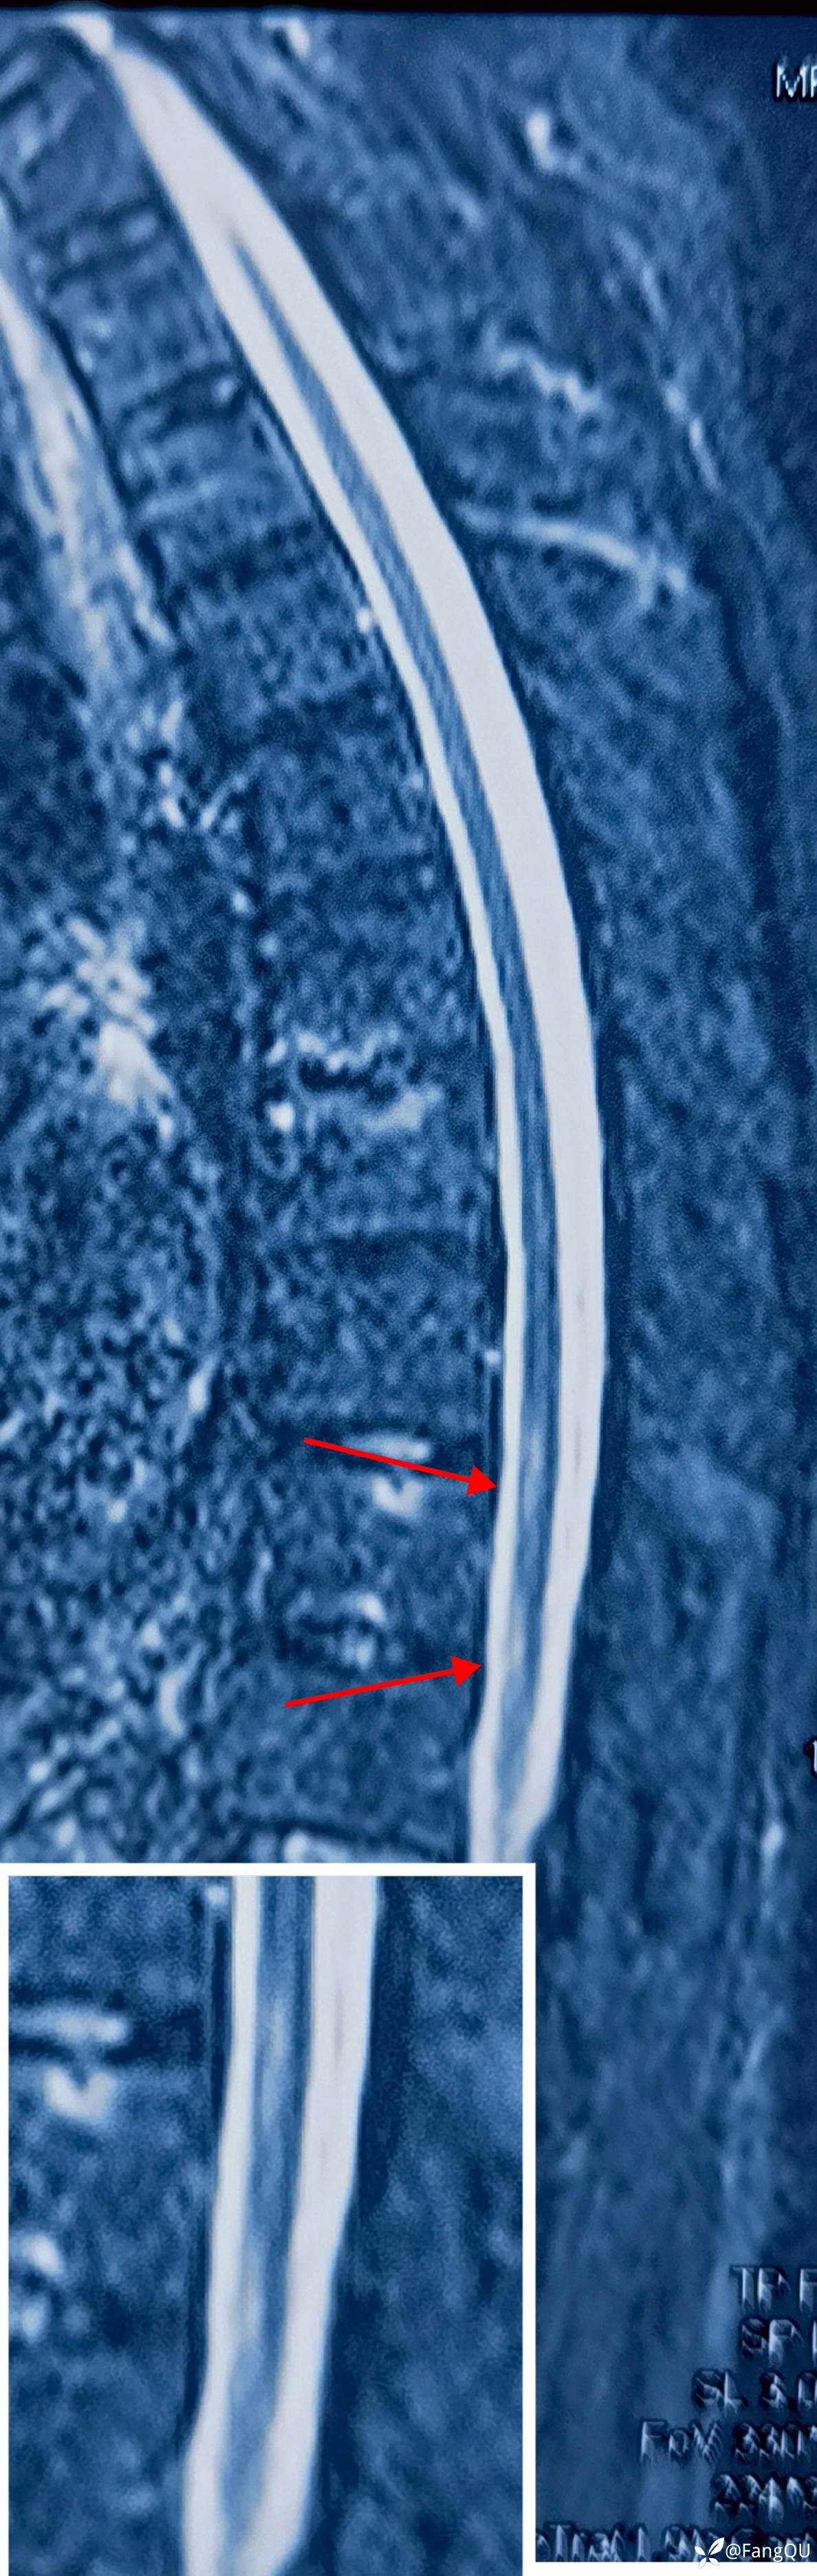

菱脑融合畸型

神经内科-神经内科

努力学English 关注

南充卫生学校2026年01月09日 23:58 20阅读 0评论 0点赞